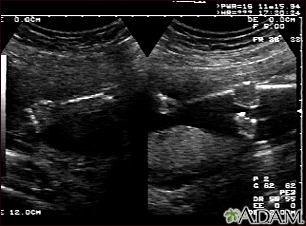

Ultrasonido normal a las 19 semanas de gestación en el cual se aprecia el tipo de proyección de la imagen en pantalla dividida que la madre puede observar durante el procedimiento, o que el técnico puede imprimir. Se observan el brazo izquierdo (al lado izquierdo de la pantalla) y las extremidades inferiores (al lado derecho de la pantalla) y las áreas blancas dentro de brazos y piernas son los huesos en formación.